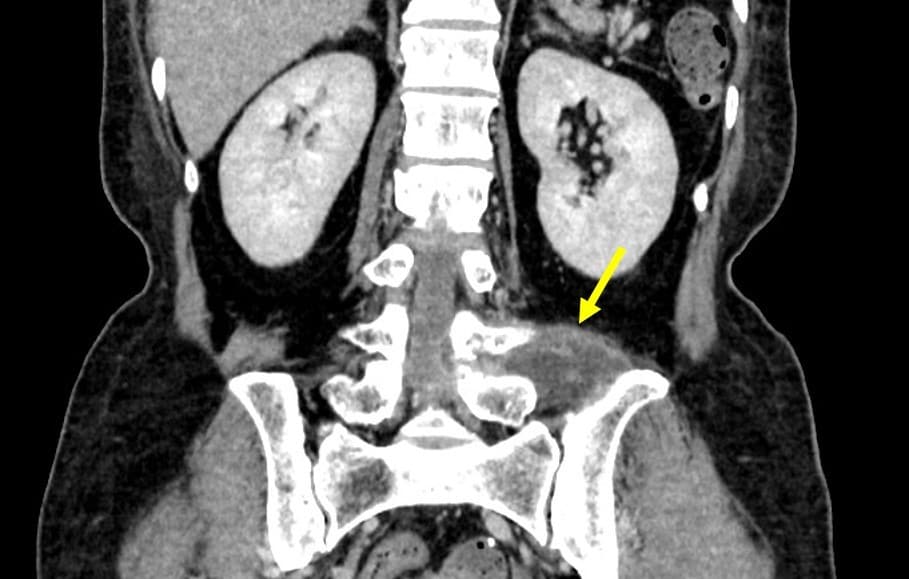

乳癌術後の再発・転移の検索目的で行われた単純CTで左腸腰筋膿瘍が疑われた。当科にCTガイド下ドレナージによる治療が依頼された。造影CTにて膿瘍は左大腰筋から左脊柱起立筋や左腰方形筋にかけて広範囲に認められた。形状は不整形で分葉状であり、辺縁に造影効果が認められ、内部は液体濃度の低吸収であり、隔壁も認められた。CTガイド下にドレナージカテーテルが膿瘍内に留置された。乳白色の膿汁がドレナージでき、ドレナージ後のCTでは膿瘍の縮小を認めた。

当該疾患の診断における造影CTの役割

腸腰筋膿瘍の症状として、発熱、腰痛、psoas positionの三主徴が知られているが、実際に全てが揃う頻度は高くない。単純CTでは診断が困難な場合もあり、熱源不明で発見が遅れることもある。造影CTでは膿瘍が検出しやすくなり、さらにドレナージを行う上でも膿瘍腔の形状や範囲が確認できるため、非常に有用である。

椎体、椎間板、結腸、虫垂、小腸、腎尿路系、膵などの隣接臓器からの炎症の波及による続発性の腸腰筋膿瘍の場合が多いため、膿瘍形成の原因検索においても造影CTは有用であると考えられる。